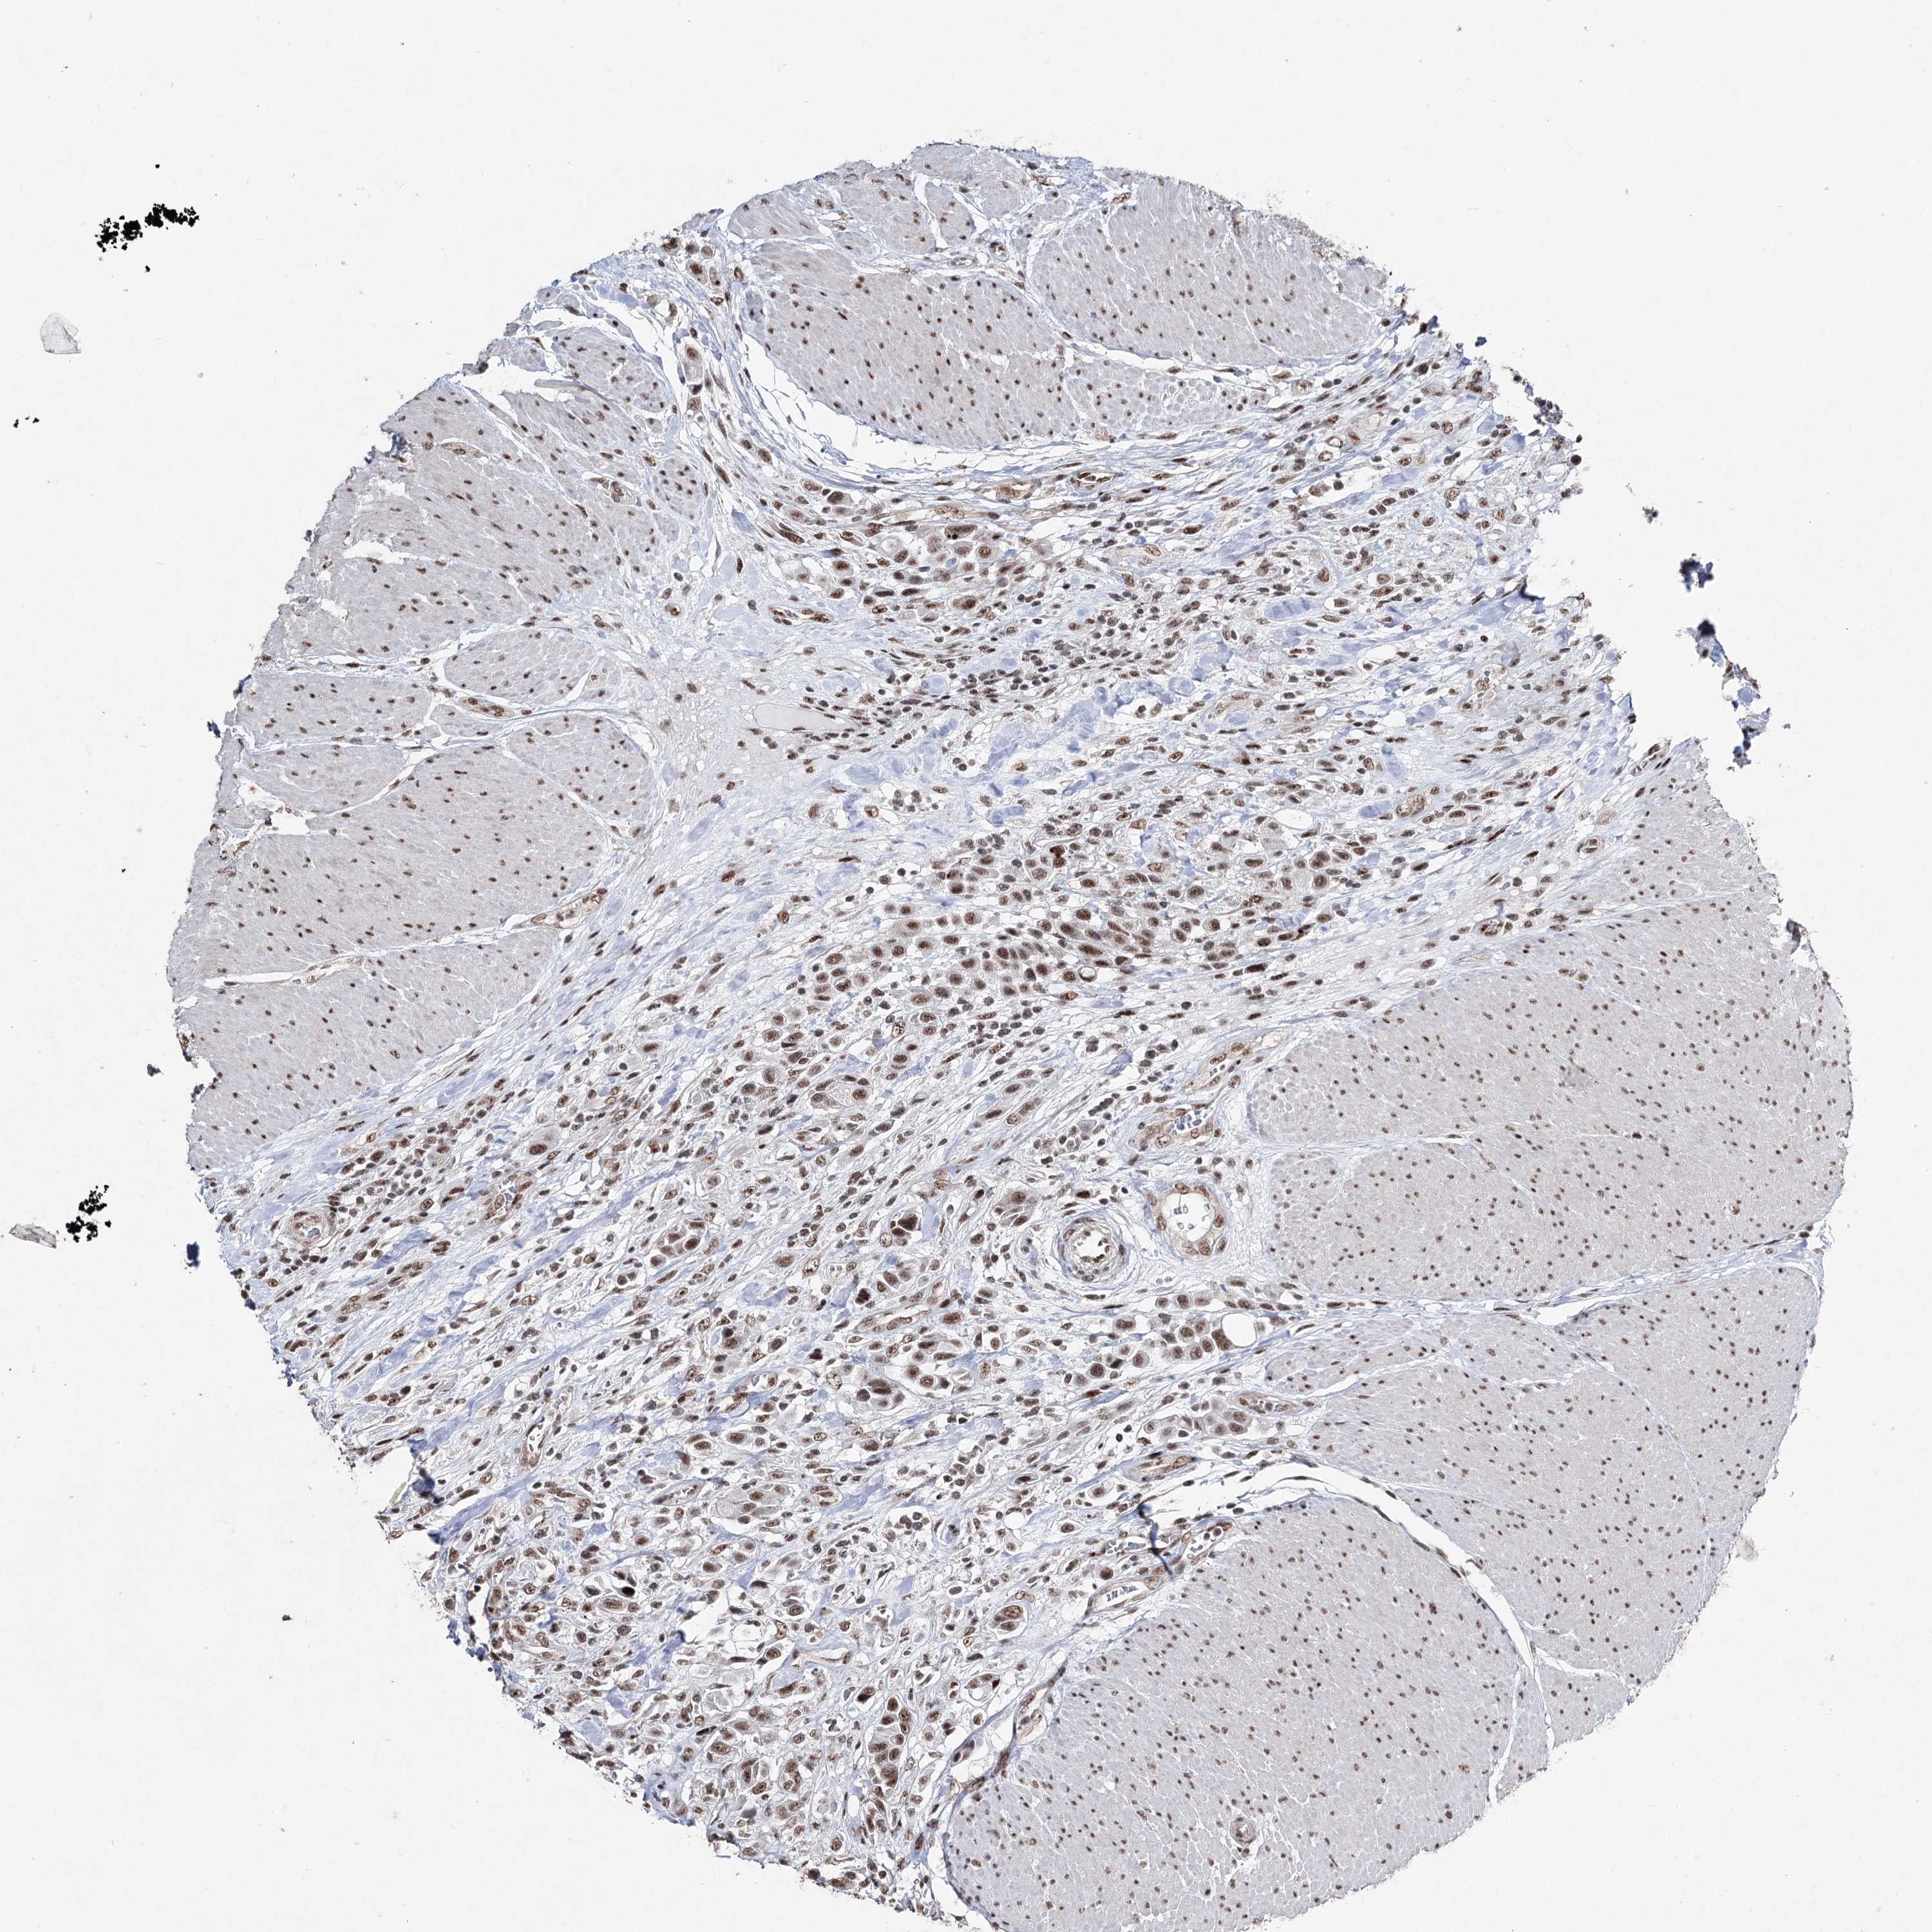

UROTHELIAL CANCER - Protein expressioni

A mouse-over function shows sample information and annotation data. Click on an image to view it in a full screen mode. Samples can be filtered based on level of antibody staining by selecting one or several of the following categories: high, medium, low and not detected. The assay and annotation is described here.

Note that samples used for immunohistochemistry by the Human Protein Atlas do not correspond to samples in the TCGA dataset.

Antibody stainingi

Antibody staining in the annotated cell types in the current human tissue is reported as not detected, low, medium, or high, based on conventional immunohistochemistry profiling in selected tissues. This score is based on the combination of the staining intensity and fraction of stained cells.

Each image is clickable and will lead to virtual microscopy that enables deeper exploration of all samples and also displays staining intensity scores, fraction scores and subcellular localization as well as patient and tissue information for each sample.

Antibody HPA001032

Antibody HPA027214

Antibody CAB037024

Urothelial carcinoma, High grade

Urothelial carcinoma, Low grade

Urothelial carcinoma, NOS